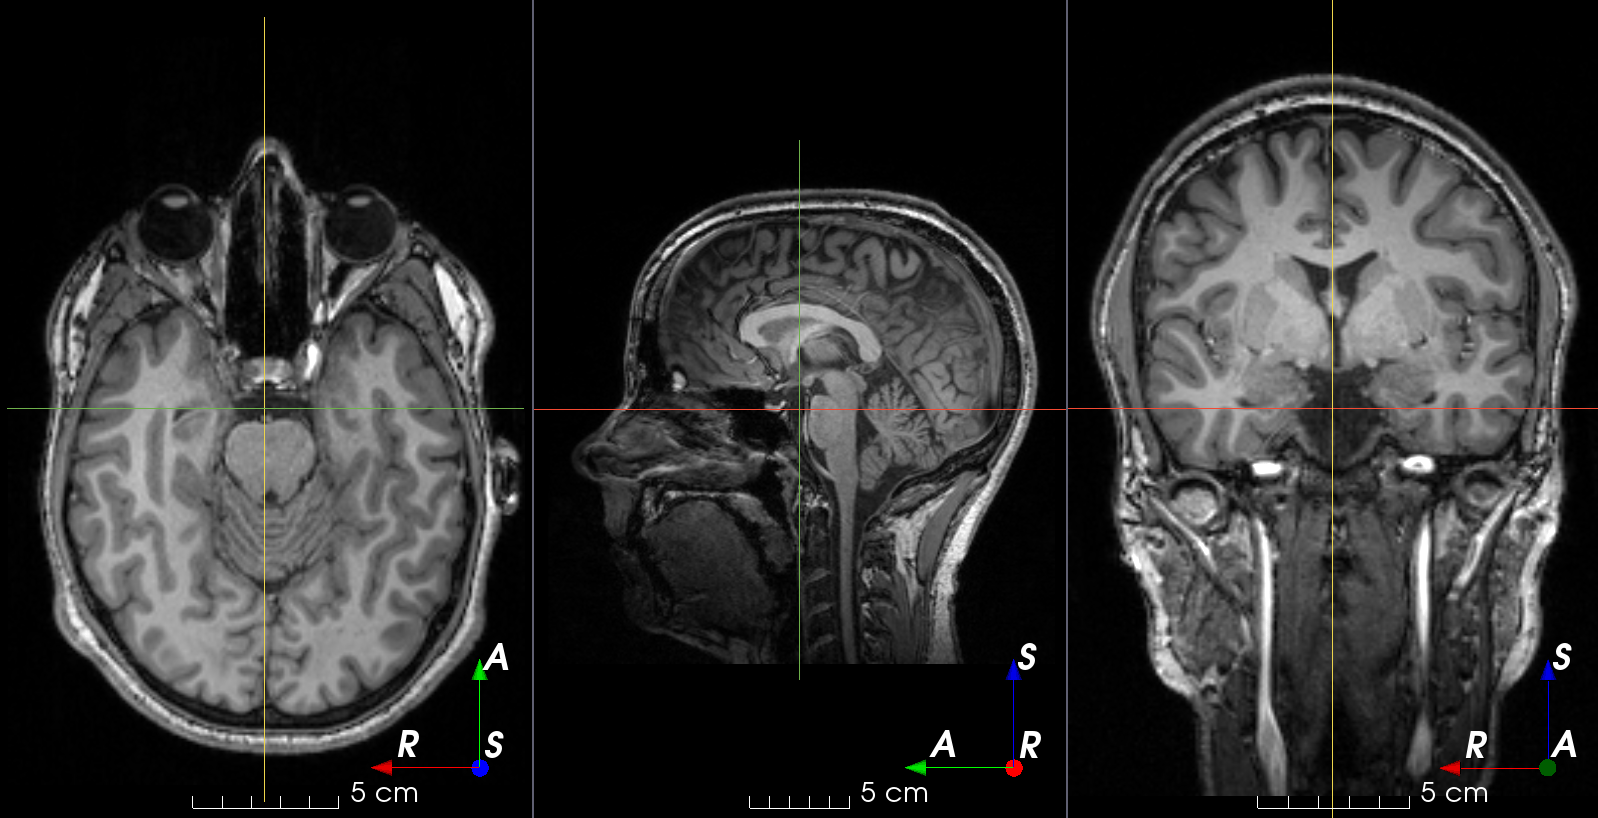

Add random MRI ghosting artifact.

Discrete "ghost" artifacts may occur along the phase-encode direction whenever the position or signal intensity of imaged structures within the field-of-view vary or move in a regular (periodic) fashion. Pulsatile flow of blood or CSF, cardiac motion, and respiratory motion are the most important patient-related causes of ghost artifacts in clinical MR imaging (from mriquestions.com).